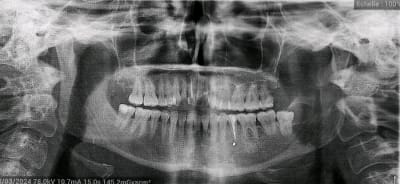

On me passe les antibios en IV, on me fait une prise de sang ( neutrophiles à 12 000 mais CRP normale) et je file voir le stomato des urgences. Il me fait un panorex (que je joins à mon message) et me dit que la douleur vient de 2 choses :

- Un morceau de "pâte" est passé dans la gencive lors du traitement définitif entraînant une inflammation (on voit la petite tâche blanche sur le panorex).

2.Retraitement canalaire. La pano n est pas précise, car l obturation semble manquer de compaction. Racine bifide ? Mais faudrait la rétro alvéolaire. Tout est supposition.

La radio fournie ici est inexploitable.

Bizarre, on ne distingue pas de couronne sur 35 sur la pano de mauvaise qualité.

Si la pano a été faite avant la couronne il ne me parait pas « bizarre » qu’elle n’y soit pas. ☝️

Concernant la couronne, le panorex a été fait après la pause de la couronne aux urgences je ne sais pas pourquoi elle n'apparaît pas ...

En regardant de plus près il y a aussi la 28 qui est bien suspecte.